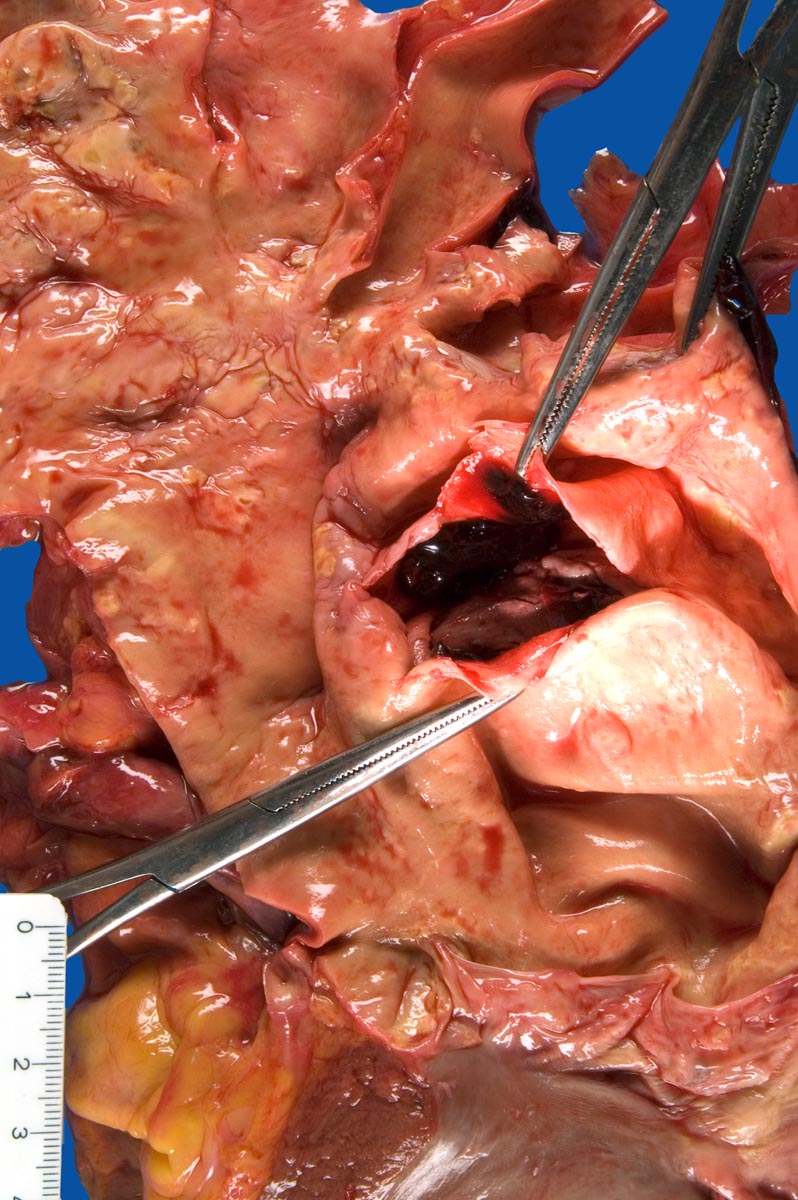

PathoPic – image database / PathoPic ID 10009 - Akutes Aneurysma dissecans der Aorta mit Ruptur

Akutes Aneurysma dissecans der Aorta mit Ruptur

Blick von ventral auf das Herz, die Aortenklappe und die Aorta ascendens mit dem von den Klammern offengehaltenen Entry 6cm oberhalb der Aortenklappe.

Aneurysma dissecans der Aorta ascendens (Typ A nach Stanford), bis zu den Arteriae iliacae communes reichend. Entry 60mm oberhalb der Aortenklappe. Re-entry des Aneurysma dissecans im Bereich der Arteria iliaca rechts. Frische Ruptur (55mm langer senkrechter Riss) im Bereich der Aorta ascendens. Einblutung in den Perikardbeutel (blutiger, zum Teil koagulierter Perikarderguss von 1000ml). Aneurysma-bedingte Kompression der A. renalis rechts und der Aorta abdominalis kurz vor der Bifurkation. Frische Einblutung in das perirenale Fettgewebe rechts und frisches Hämatom im Bereich des Musculus psoas rechts (ca. 300ml).